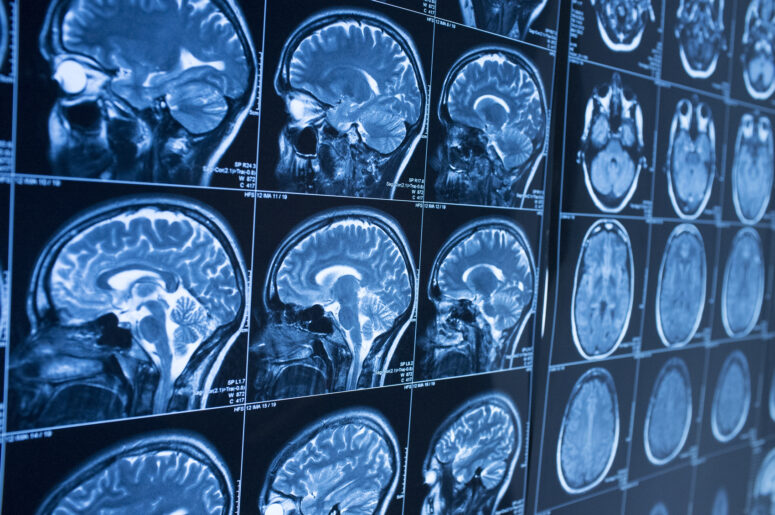

A recent study published in Neuropsychological Rehabilitation looked at severe brain injury patients and found that they have “music evoked autobiographical memories” (MEAMs) in the same way that healthy people do.

The patients often associated the music with certain memories from their lives. In addition, some patients had strong emotional reactions to the songs. The study was small, only looking at five patients to start. One patient was seriously injured in a motorcycle crash and couldn’t remember many parts of his life. A second patient attempted suicide and suffered from permanent brain damage as a result.

The study’s author, a clinical neuropsychologist, said that music might be useful as a tool for people with memory problems after suffering a brain injury. The study authors also noted that music might be a potential therapy tool for patients with neurological issues, including Alzheimer’s disease.